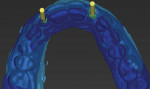

A diagnostic (light blue image) wax-up, which was scanned by the Straumann CS2 in-lab scanner (www.straumann.us), was used to generate a .stl file that was overlaid with the coDiagnostiX scan (dark blue image) and an Align Technology iTero® (www.aligntech.com) digital impression file to visualize the current dentition and facilitate planning for the ideal restorative outcome (Figure 3).